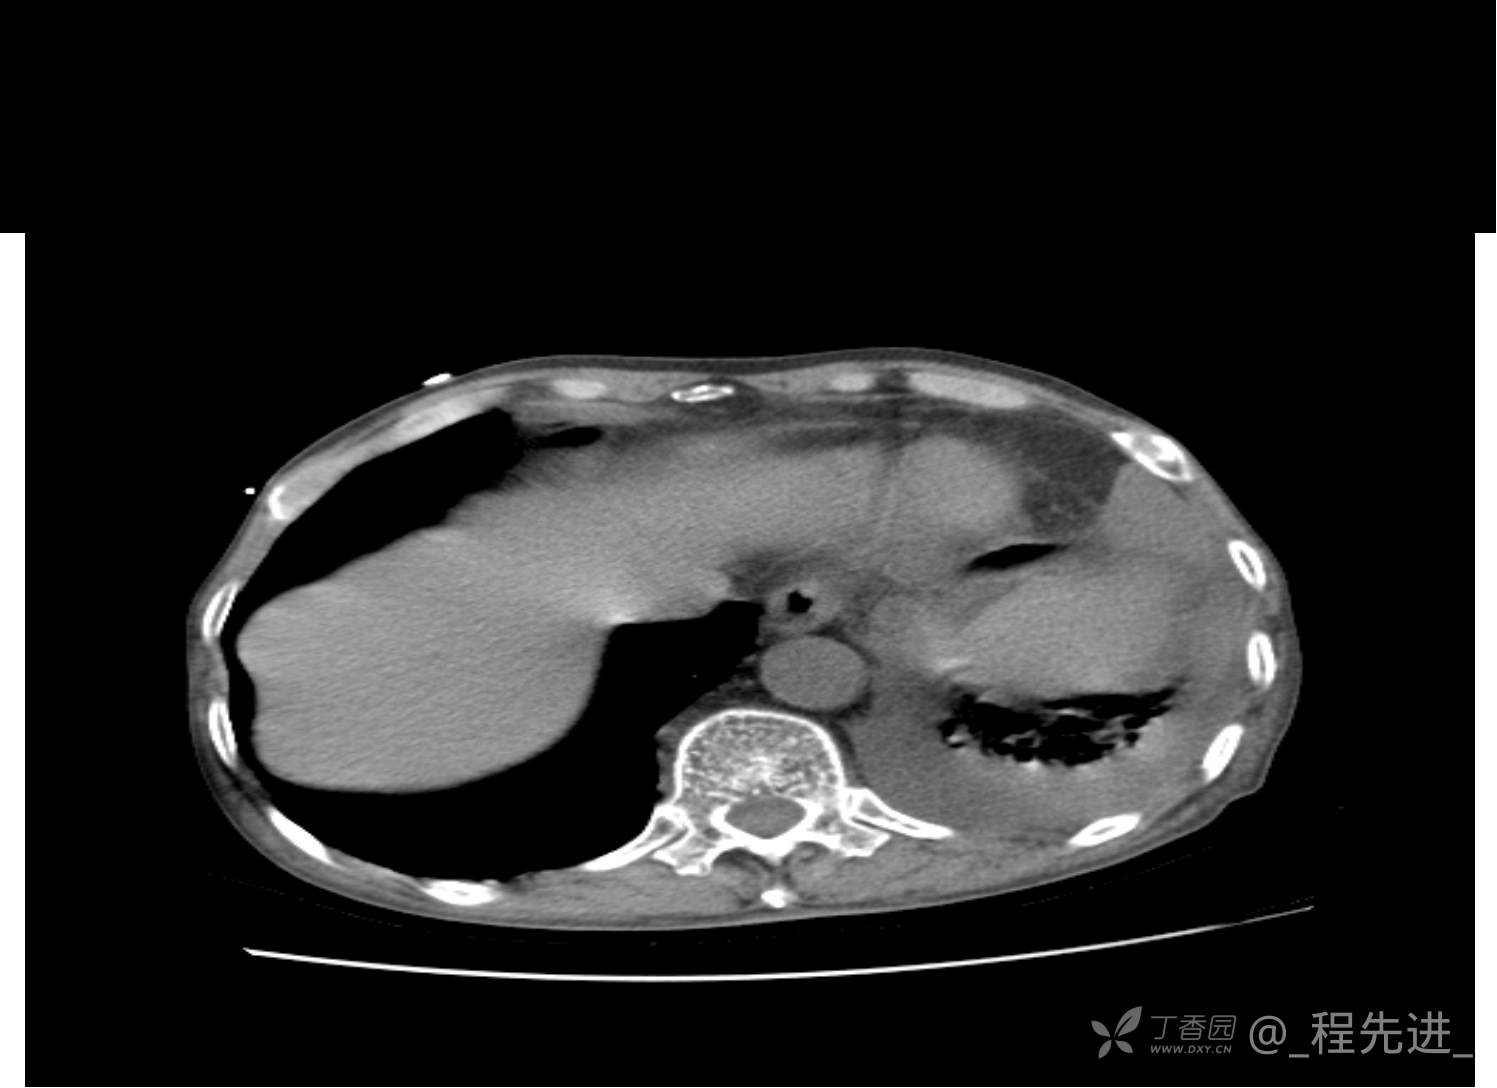

患者性别:男

患者年龄:81岁

简要病史:反复咳嗽、咳痰20余年,加重1周。两肺呼吸音低,可闻及散在干湿啰音。